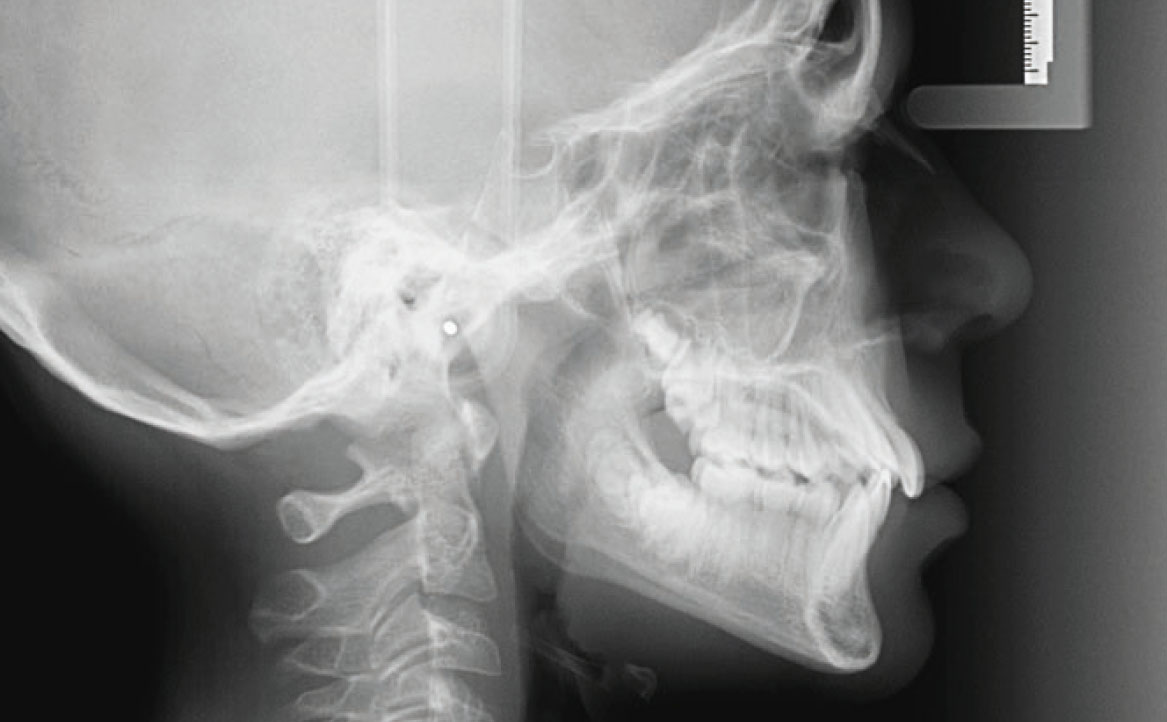

Inoltre, dall’analisi del volto si evidenziava la presenza di una mandibola leggermente retrusa. Ciò è stato confermato dalla teleradiografia latero-laterale, attraverso la quale è stata osservata una condizione di normo-divergenza con una tendenza all’iper-divergenza, con una condizione di seconda classe scheletrica, valutando gli angoli SNB ed ANB, le cui misure risultano essere rispettivamente di 75,5° e 4,5° (fig. 2).

La teleradiografia latero-laterale confermava il sospetto di una seconda classe scheletrica, con angoli SNB e ANB rispettivamente di 77° e 5°, con un aumento della pro-inclinazione degli incisivi superiore e un aumento dell’overjet, corrispondente a circa 6 mm (fig. 6).